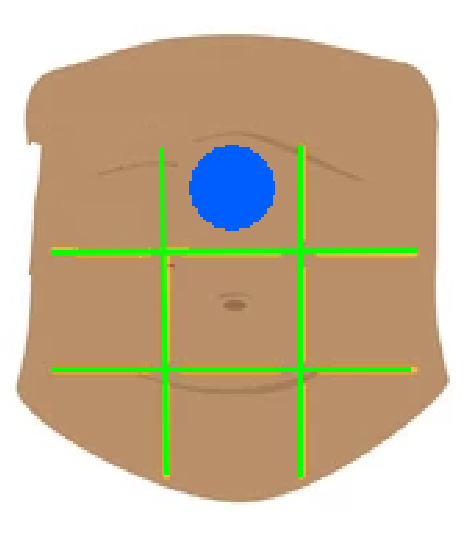

Right hypochondriac region

Left hypochondriac region

Epigastric region

Right lumbar region

Left lumbar region

Umbilical region

Right inguinal region

Left inguinal region

Hypogastric regions